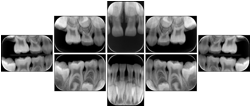

2. A patient requests cosmetic surgery to enhance their facial appearance. The case requires consultation between an orthodontist in New York and an oral surgeon in California. The cephalometric series of 2D projections constructed from a volumetric CT data set that is used for the discussion is arranged by a Structured Display for transfer between the two practitioners.

Cephalometric Series Structured Display

Figure OO-2. Cephalometric Series Structured Display